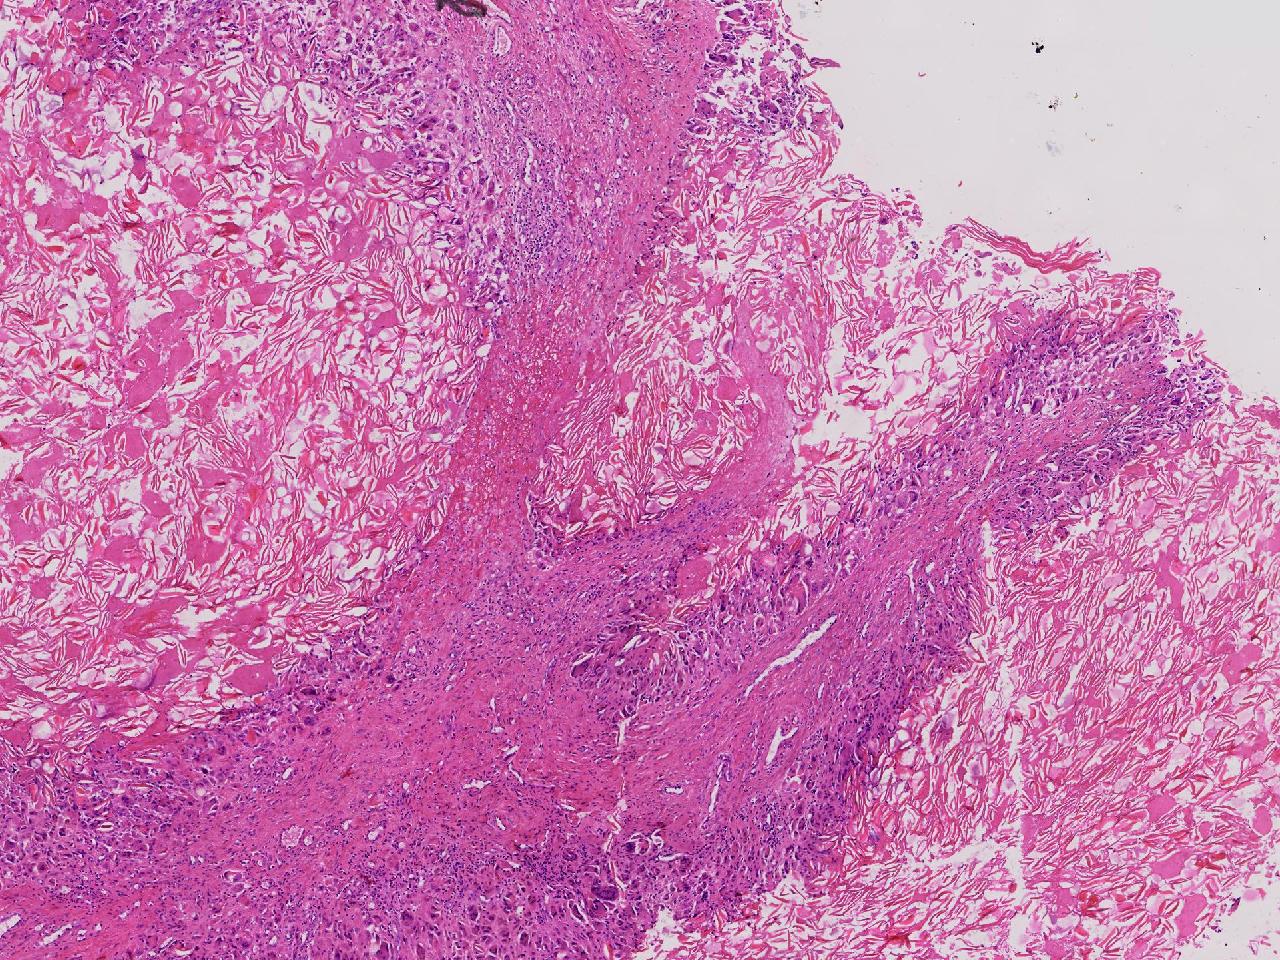

皮样/表皮样囊肿伴周边异物巨细胞反应?

右侧臀部皮下肿物10余年,渐增大,无破溃,无疼痛。

右侧臀部皮下肿物

囊性肿物一个,直径2.5厘米,肿物位于皮下。

异物肉芽肿性炎?

表皮样囊肿伴异物肉芽肿性炎。